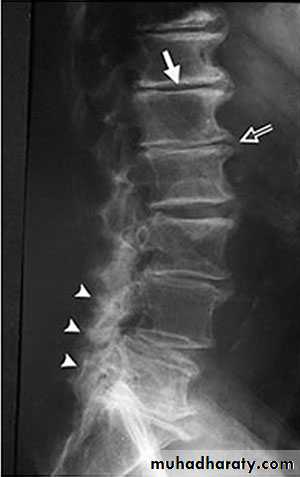

X-rays: show an abnormal narrowed disc space and to exclude bone diseases. After several attacks the disc space may be narrowed and small osteophytes appear.CT and MRI are more reliable than myelography.

X-Rays:

Flattening of the disc space and marginal osteophyte formation appear later.• CHRONIC INTERVERTEBRAL DISC DEGENERATION

X-ray:Lateral views show the forward shift of the vertebra above on the vertebra below.

The gap in the pars interarticularis is best seen in the oblique views.